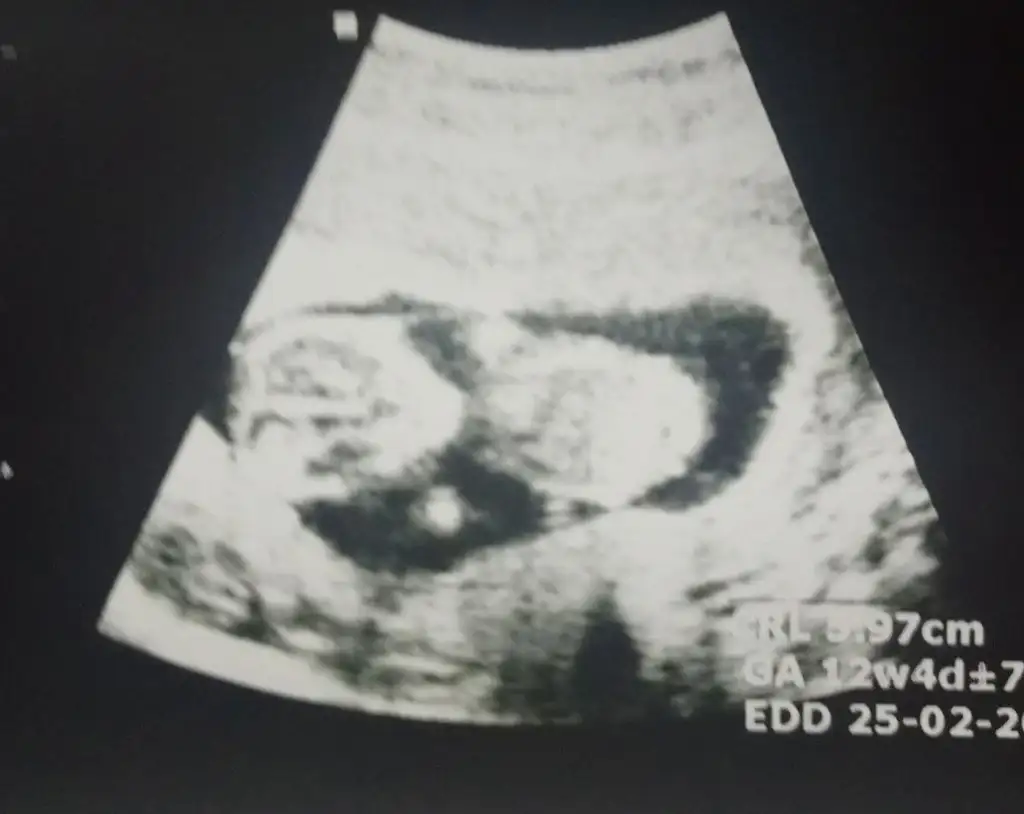

Merhaba 12 haftalik ultrason goruntusuu sizce kizmi erkekmi😍😍